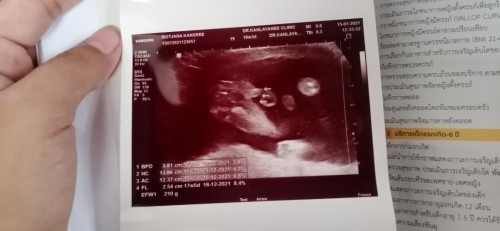

อายุครรภ์17w ยังไม่ค่อยแน่นอนเท่าไรนะคุณแม่ อดใจรอซาวด์ซ้ำตอนอายุเยอะกว่านี้อีกหน่อยจะชัดเจนกว่าจ้า ของเรา19w หมอบอกอาจจะหญิง แต่หมอบอกว่าจะซาวด์ให้อีกทีตอน 24wจ้าแม่

ชายนะคะ ตรงลูกศรคือช้างน้อย☺